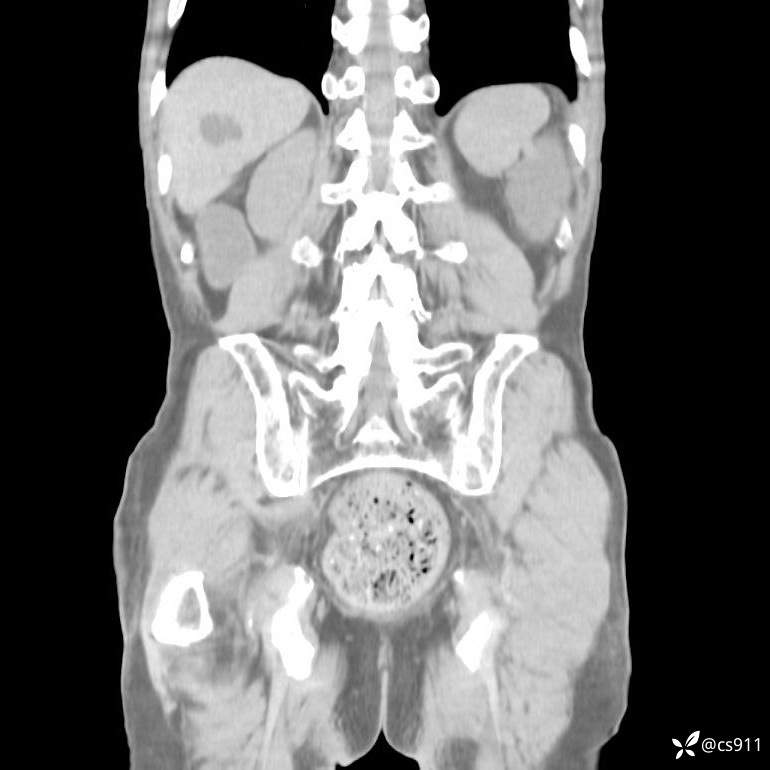

急腹症之急诊CT,原因?答案公布

男,77岁,腹痛、腹胀伴恶心呕吐1天。呕吐胃内容物,非喷射性呕吐,有咖啡色样胃内容物,诉有胃穿孔病史。查体:全腹平,下腹部压痛,全腹无反跳痛,叩诊呈浊音,移动性浊音阴性,肠鸣音减弱,1-2次/分。肛检:直肠未扪及明显肿物,可触及大量粪块。

血淀粉酶(AMY) HH 1859 U/L 35-135

癌胚抗原(CEA) H 27.44 ng/ml 0-5